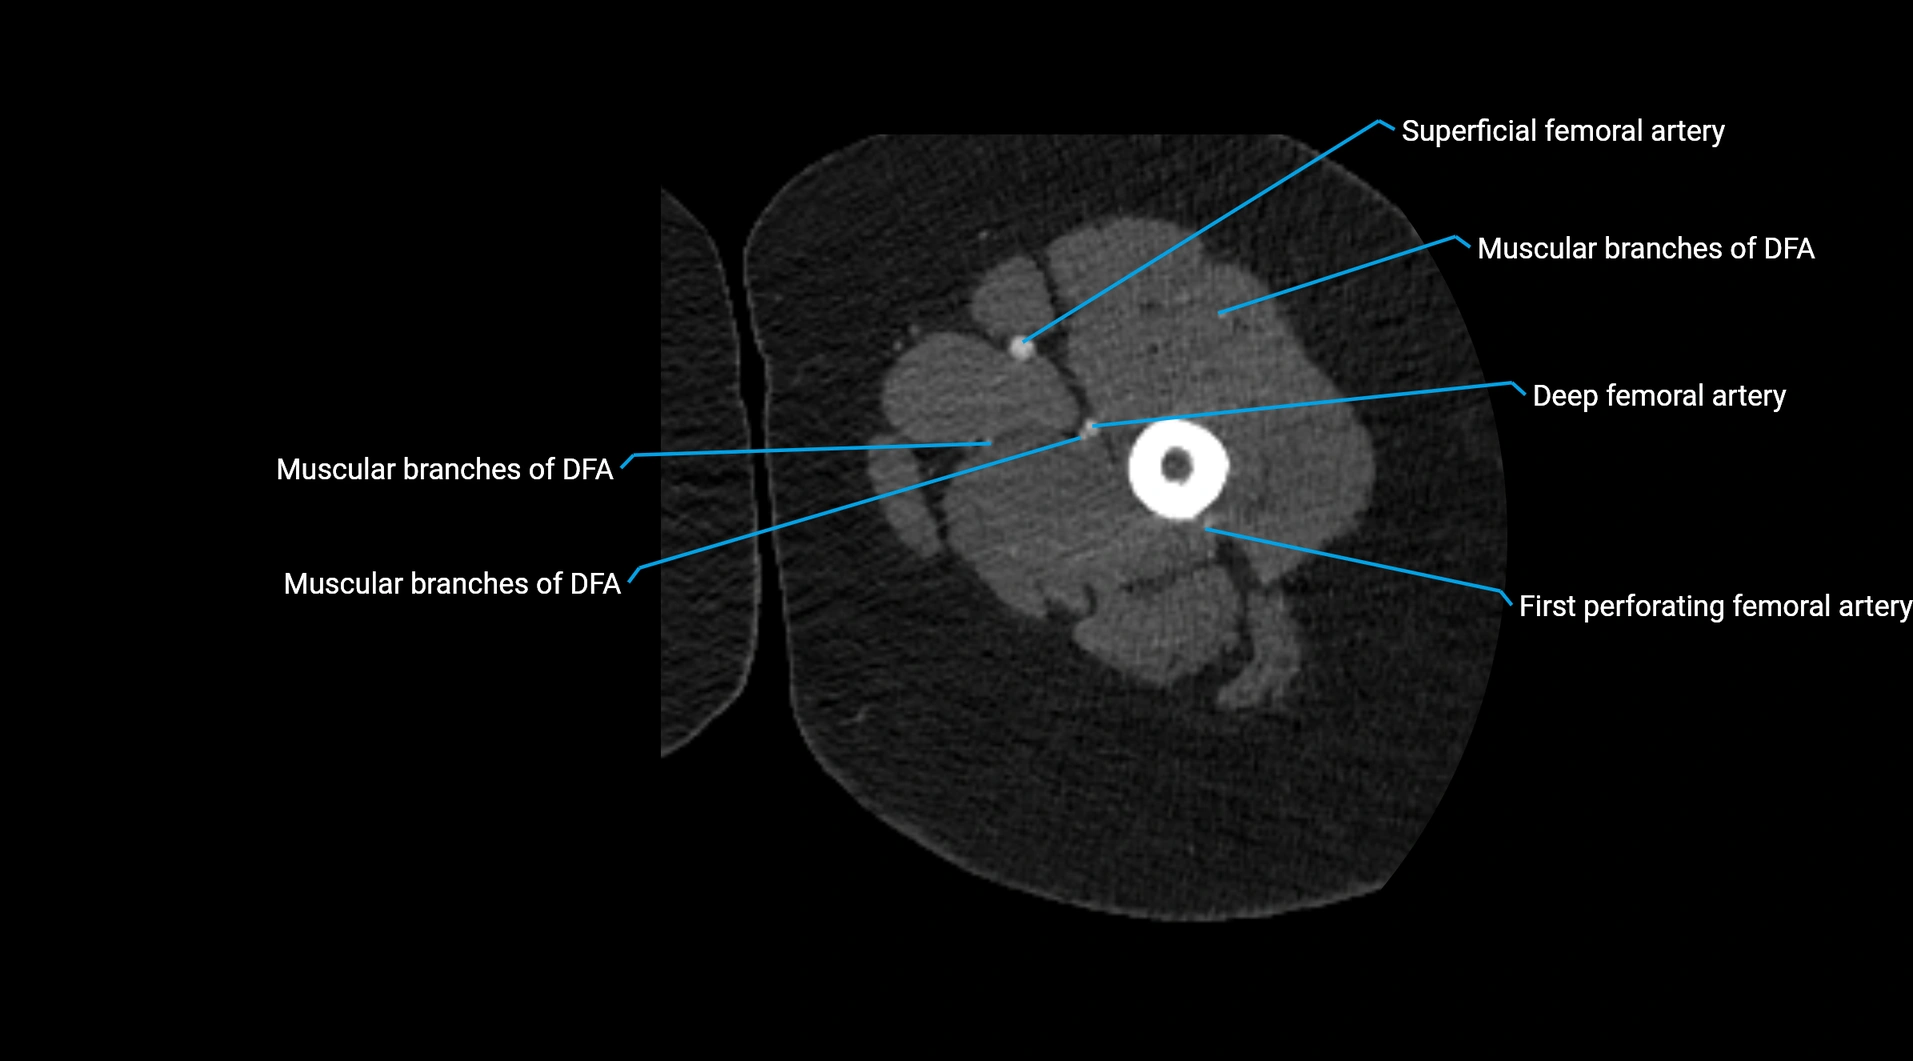

CT Appearance

Non-contrast CT:

• Appears as a tubular soft tissue structure anterior to vertebral bodies

• Calcified atherosclerotic plaques appear as hyperdense foci along the wall

• Useful for screening abdominal aortic aneurysm (AAA) size and mural calcification

Contrast-enhanced CT (CTA):

• Gold standard for abdominal aortic imaging

• Provides excellent detail of lumen, wall, aneurysm, thrombus, and branch vessels

• Multiplanar and 3D reconstructions help in aneurysm measurement, stent graft planning, and dissection evaluation

• Detects acute rupture, traumatic injury, or occlusion with high sensitivity